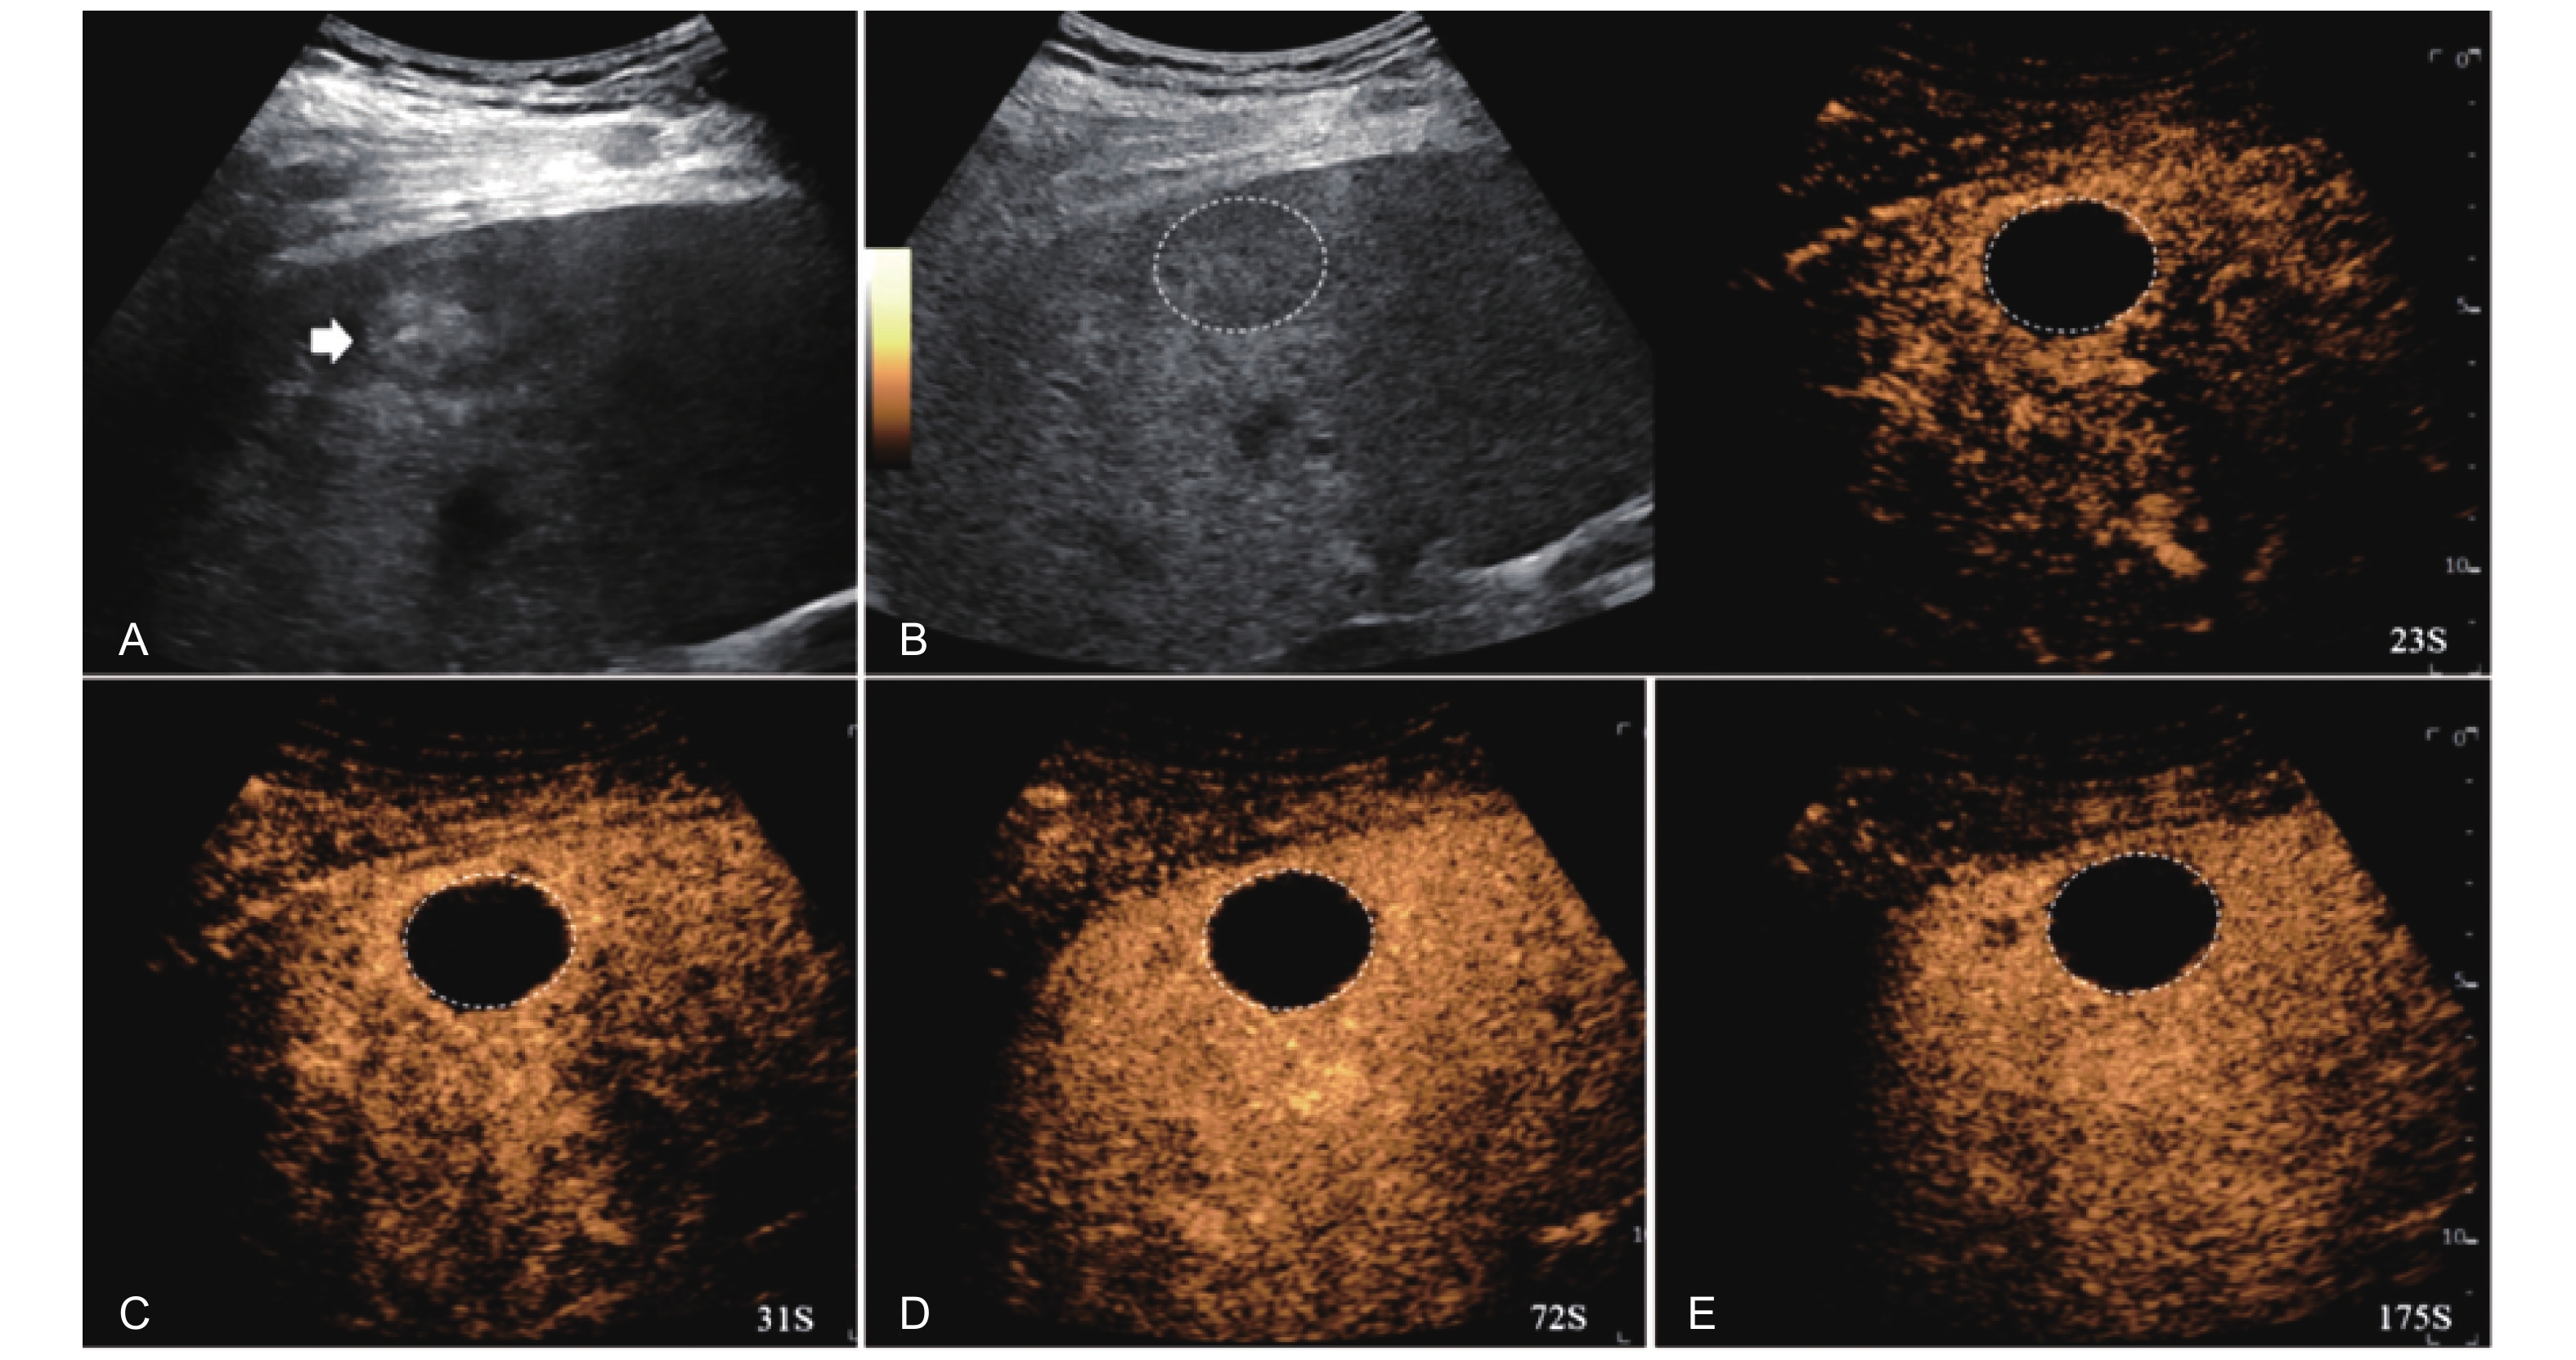

Figure 4

LR-TR Nonviable. Example of a nonviable tumor 14 days after TACE. (A) B-mode image shows two heterogeneous hyperechoic lesions (thick arrow) with irregular shape, measuring 17 mm and 18 mm in segment VI; (B-E) CEUS shows no intralesional enhancement with perilesional enhancement identical to the surrounding liver parenchyma in all phases. Findings are consistent with LR-TR Nonviable."